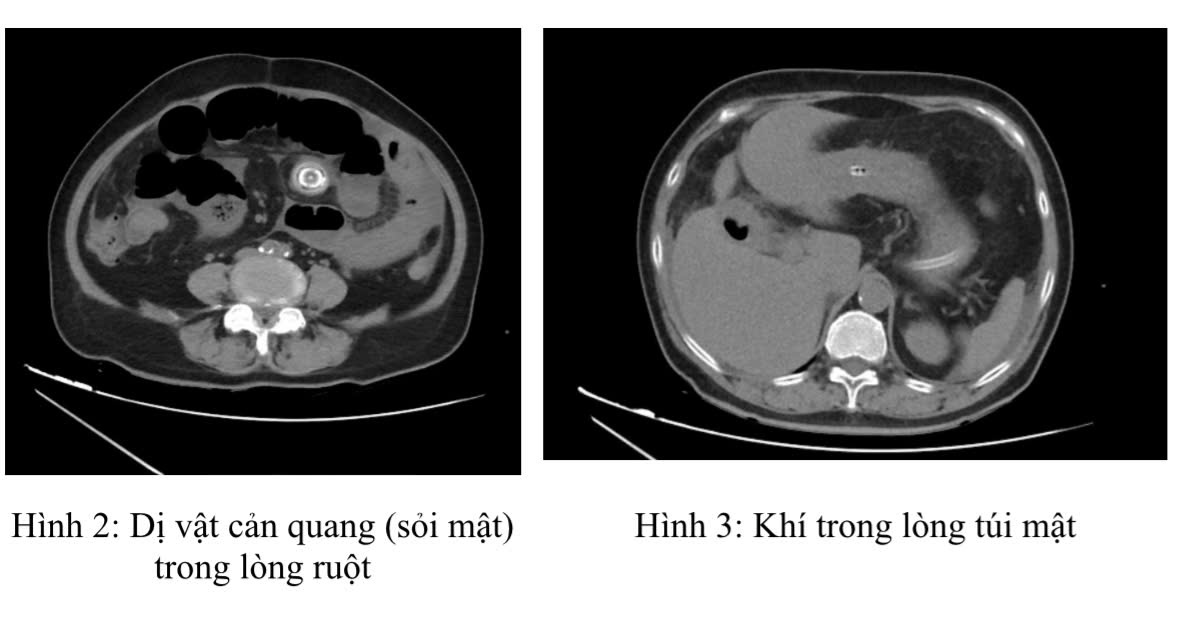

Ngay lập tức, các bác sĩ của Trung tâm Phẫu thuật Tiêu hóa đã tiến hành các thăm dò cần thiết. Kết quả X-quang bụng không chuẩn bị cho thấy dấu hiệu các quai ruột giãn hơi. Chụp cắt lớp vi tính ổ bụng (CT scan) đã xác định rõ ràng tình trạng tắc ruột. Hình ảnh CT cho thấy giãn các quai ruột non quanh rốn kích thước 36mm có mức dịch khí, vị trí chuyển tiếp có dị vật cản quang hình tròn kích thước 23mm. Đồng thời, túi mật thành dày nhẹ, chứa khí có đường thông với tá tràng. Đây chính là “bộ ba dấu hiệu Rigler” điển hình của tắc ruột do sỏi mật, bao gồm: hình ảnh khí trong đường mật (pneumobilia); tắc ruột non với mức nước-khí; và hình ảnh sỏi mật lạc chỗ trong lòng ruột.

Với chẩn đoán xác định tắc ruột do sỏi mật/Đái tháo đường, Parkinson, bệnh nhân được đặt sonde dạ dày, truyền dịch, kháng sinh trước mổ để ổn định tình trạng. Sau một ngày điều trị nội khoa, bệnh nhân được phẫu thuật. Quá trình trong mổ, các phẫu thuật viên phát hiện trong ổ bụng có 500ml dịch vàng trong, các quai ruột non giãn ứ đọng hơi và dịch, cách góc hồi manh tràng 1m có dị vật cứng chiếm hết lòng ruột, quai ruột phía sau xẹp. Túi mật viêm teo dính vào tá tràng có đường rò túi mật hành tá tràng mặt trước kích thước 2cm. Viên sỏi túi mật hình tròn màu xanh đen kích thước khoảng 25mm đã được lấy ra khỏi lòng ruột.